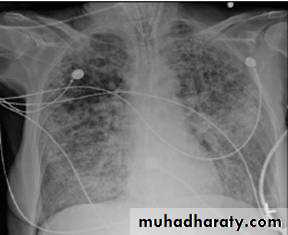

Imaging Studies

The chest radiograph reveals characteristic diffuse bilateral alveolar-interstitial infiltrates.In early cases, the radiographic findings may not be fully developed.

Additional localized pulmonary findings may be present if the predisposing condition involves a pulmonary process.